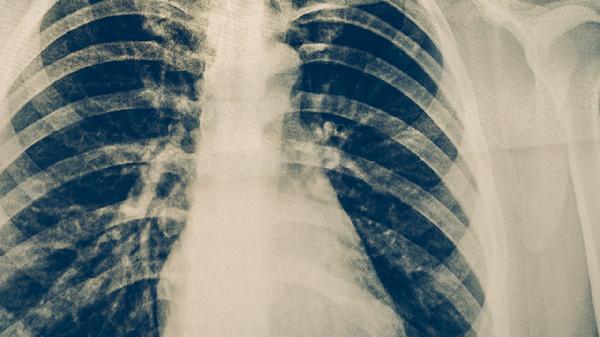

3、影像学特征

肺结核在胸片上多表现为上叶尖后段或下叶背段的浸润性病变,可伴有空洞形成。肺癌在影像学上多表现为孤立性结节或肿块,边缘不规则,可能伴有毛刺征、分叶征等恶性征象。